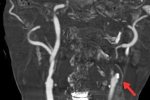

周伯翰立即安排王翁轉急診做電腦斷層,發現其左側前額葉出現急性腦出血,經與神經外科醫師江忠穎與急診室安排緊急住院,經仔細治療,生命狀況回穩並順利出院